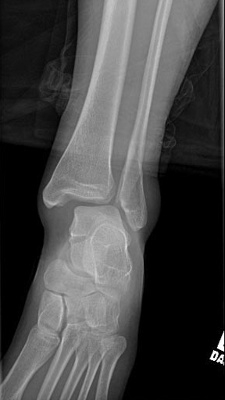

Before and After Image

After receiving imaging of your ankle, if the ankle fracture is displaced, or the ankle feels unstable, surgery may be required to fix the fracture.

After the surgery, the ankle will be placed in a cast or boot for several weeks. The doctor will follow up with multiple X-Rays to ensure good recovery progress. Patients attend physical therapy for the duration of their recovery process. Full healing of the fracture takes 8 weeks. Patients start attending physical therapy when instructed by their physician and continue for the duration of their recovery process.